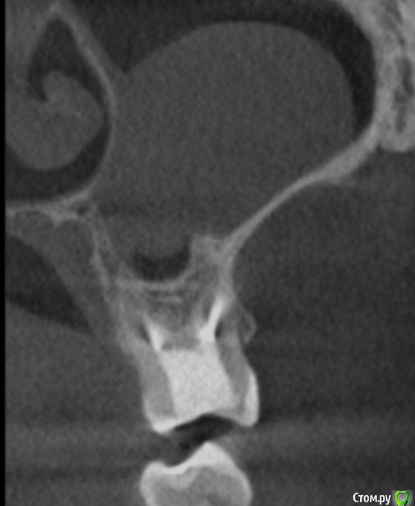

tineola Опубликовано 15 марта, 2017 Автор Поделиться Опубликовано 15 марта, 2017 (изменено) Сделала несколько скриншотов, прикрепляю к сообщению. Надеюсь, это то, что нужно.Может у кого-то из врачей будет время и возможность посмотреть КТ (ссылка в первом сообщении поста). Получила результаты гистологии первой кисты пазухи, которая год назад была удалена:Микроописание: Присланный материал представлен фрагментом полипозно-отечной слизистой оболочки, с концевым отделами слизисто-серозных желез. Эпителий слущен, гиалиоз базальных мембран, строма резко отечна, с диффузной лимфоцитарно-лейкоцитарной инфильтрацией. Патзаключение: хронический воспалительный процесс. Изменено 15 марта, 2017 пользователем tineola Ссылка на комментарий

tineola Опубликовано 15 марта, 2017 Автор Поделиться Опубликовано 15 марта, 2017 Еще скриншоты. Другая проекция из КТ. Ссылка на комментарий